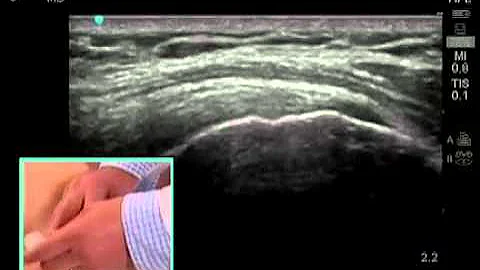

Webinar: Ultrasound-guided Shoulder Injections Part 1